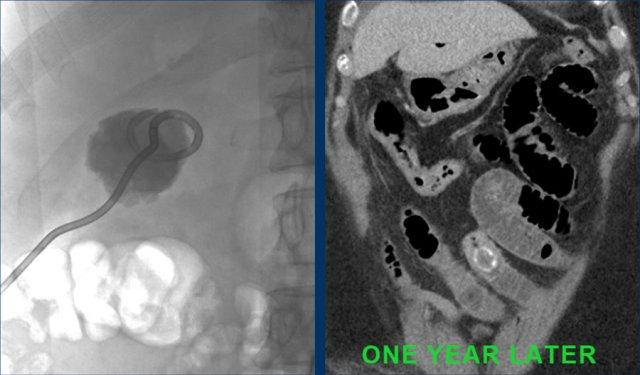

Đây là bệnh nhân có tình trạng ứ đọng dạ dày từng đợt và CRP thấp.

Một viên sỏi lớn bị “kẹt” trong đường rò từ túi mật biến dạng đến tá tràng.

Dày thành tá tràng thứ phát (đầu mũi tên) cùng mô viêm và mô xơ xung quanh gây ra tình trạng ứ đọng dạ dày từng đợt kèm nôn mửa.

Hình ảnh của một bệnh nhân nữ cao tuổi, nhập viện vì ứ đọng dạ dày và nôn mửa.

CRP là 55, nhưng được ghi nhận là 160 vài ngày trước đó.

Siêu âm cho thấy một viên sỏi lớn trong túi mật chứa đầy chất lắng cặn, thành túi mật không đều.

Dạ dày giãn to và có dày thành tá tràng đáng kể (đầu mũi tên) kèm viêm xung quanh (dấu hoa thị).

Nội soi dạ dày được thực hiện do nghi ngờ ác tính, nhưng sinh thiết chỉ cho thấy hình ảnh viêm.

Tiếp tục xem CT.

CT xác nhận chẩn đoán hội chứng Bouveret.

Dẫn lưu túi mật qua da đã giải quyết các triệu chứng ứ đọng dạ dày.

Một năm sau, viên sỏi dường như đã tự di chuyển vào lòng tá tràng, và bệnh nhân phát triển tắc ruột do sỏi mật điển hình, được phẫu thuật thành công.